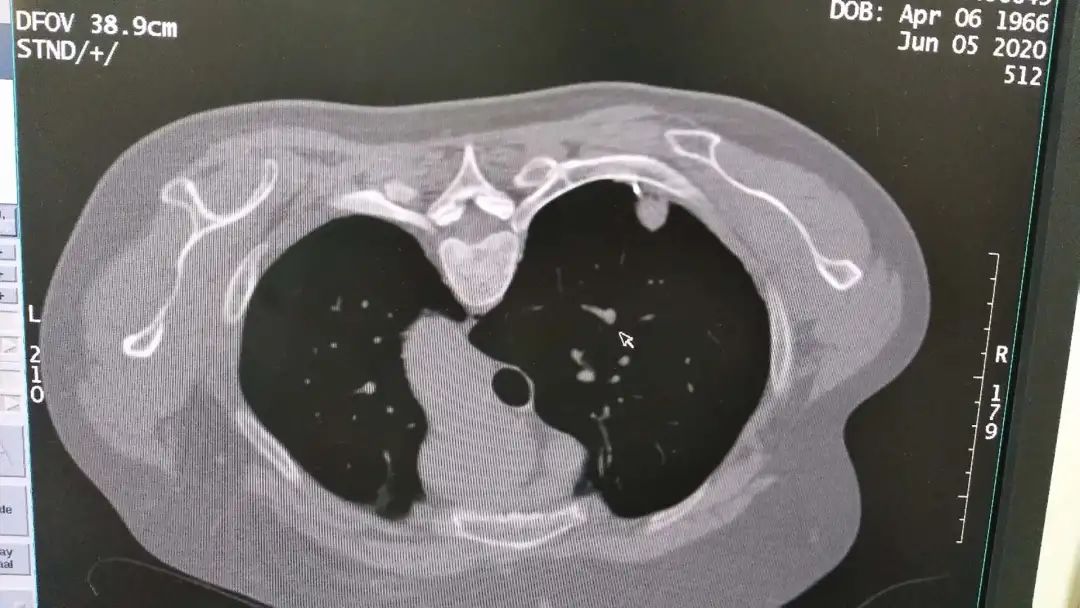

图 自制带角度定位栅栏在CT引导下经皮肺穿刺活检技术的应用

其中,该科所拥有的自制带角度定位栅栏在CT引导下经皮肺穿刺活检技术,该技术适用于肺部有病变的患者,如肿块,结节,软组织病变的患者,通过边做CT,并在自制带角度定位栅栏定位下,使得以往不易确定进针部位,能够精准确定肺部肿块进针穿刺位点。

今年5月,在病友介绍下,金女士专程来到市中心医院,找到该院肿瘤科主任舒诚荣和章永医师,希望能得到两位医师的帮助。为了解除金大姐这块心病,两位医师在仔细阅片后,决定尝试使用自制带角度定位栅栏在CT引导下采取非共面经皮肺穿刺活检。

与往常此类手术所不同的是,本次手术采用了医院章永医师所研制出的拥有一项自制带角度定位栅栏在CT引导下经皮肺穿刺活检技术的应用的新技术,让穿刺位点不易进针的难题迎刃而解。